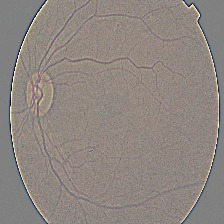

What it does: AI Cura utilizes artificial intelligence to predict diabetic retinopathy and kidney diseases in diabetic patients, offering accurate and timely diagnostic capabilities. By analyzing medical imaging data and biomarkers, AI Cura enables proactive interventions and personalized treatment plans, revolutionizing diabetic care.

How we built it: Research Paper Used- https://www.aao.org/eye-health/diseases/what-is-diabetic-retinopathy The development of AI Cura involved leveraging deep learning algorithms and advanced image processing techniques. We curated extensive datasets comprising diverse medical images and patient profiles, trained AI models to recognize disease patterns, and rigorously validated their performance across different patient cohorts and imaging modalities.